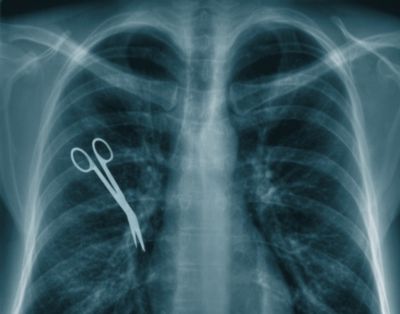

Qarın nahisəsində yenidən ağrılar hiss edən qadın rentgen müayinəsindən keçəndə, nə o gözlərinə inana bilib, nə də həkimlər. Onun qarın boşluğunda tibbi alətin olduğunu görən cərrahlar Xanım Özgülü yenidən əməliyyat edərək metal əşyanı çıxarıblar.

4 övlad anası olan Xanım Özgül xərçəng xəstəliyi ilə mübarizə apardığından, cərrahlar təhlükəli hüceyrələrin bədəndən kəsilərək çıxarılmasına qərar verib. Qadının bətnində aparılan əməliyyat uğurlu keçsə də, onun fəsadları 5 il sonra məlum olub. Sən demə həkimlər, damar tutmaq üçün istifadə olunan aləti, əməliyyatın sonunda qadının qarnından çıxarmağı unudub. Əməliyyatdan sonra yaralaları sağalan 67 yaşlı qadın evə buraxılıb və o 5 il qarnındakı metal alətlə yaşayıb.

Cərrahlar səhvlərini 5 il sonra düzəltsələr də, zərərçəkənin ailəsi xəstəxananı məhkəməyə verib. Həkimlərin günahı sübuta yetirilsə, onda xəstəxana rəhbərliyi Özgül ailəsinə təzminat ödəmək məcburiyyətində qalacaq.